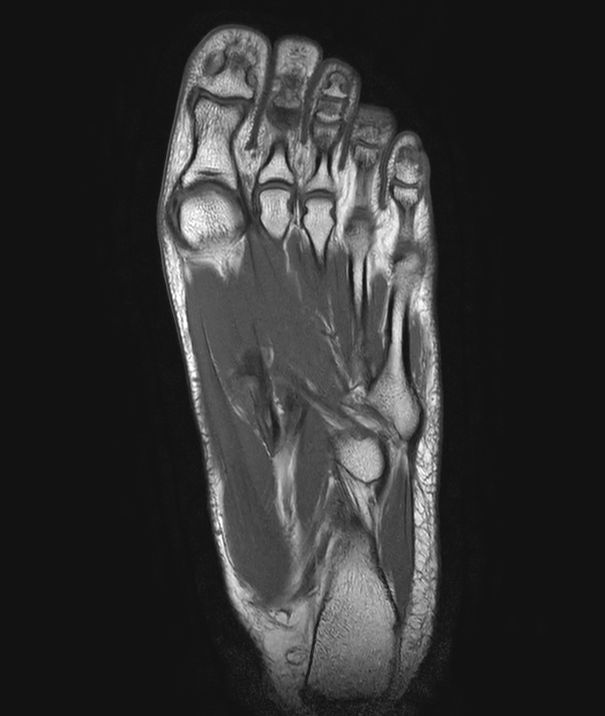

SmartSpeed Forefoot imaging

Suzukake Central Hospital, Japan

This forefoot ExamCard includes 3 orientations and several different contrasts. SmartSpeed is used to increase imaging speed while delivering outstanding image quality.

Sagittal T2w TSE

-

Sagittal T1w TSE

Sagittal STIR TSE

Coronal T2w TSE